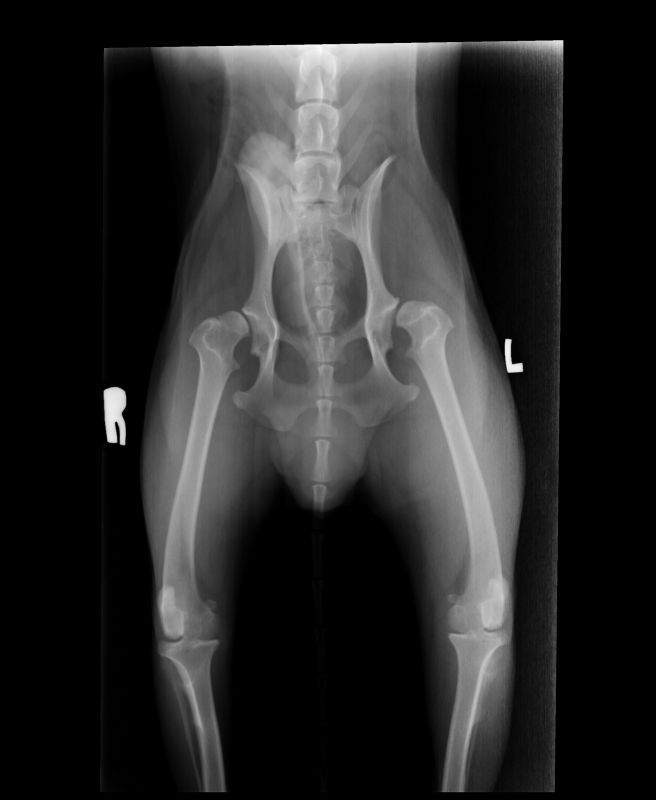

Abnormal Pathology on your pet

Shown on x-ray images which we have taken over the years.

Some interesting patient cases